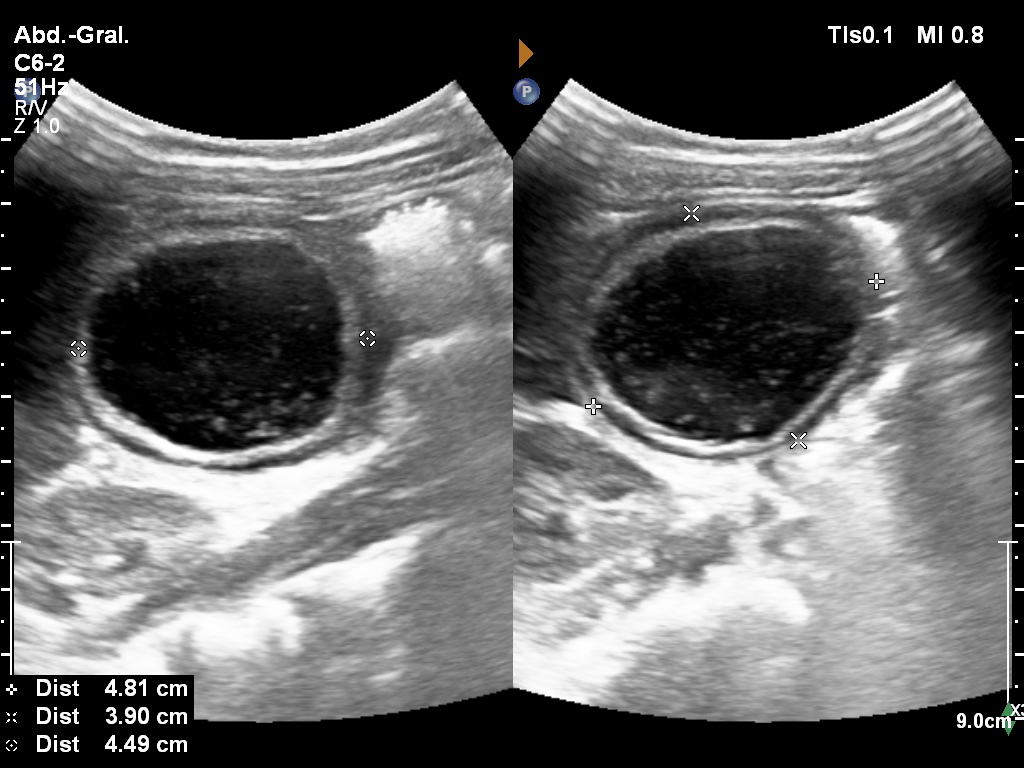

Paciente de 12 años con dolor abdominal. Remitida para estudio de masa intraabdominal.